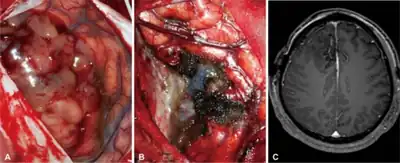

Surgery

The primary and most desired course of action described in medical literature is surgical removal (resection) via craniotomy. Minimally invasive techniques are becoming the dominant trend in neurosurgical oncology.[47] The main objective of surgery is to remove as many tumor cells as possible, with complete removal being the best outcome and cytoreduction ("debulking") of the tumor otherwise. In some cases access to the tumor is impossible and impedes or prohibits surgery.

Many meningiomas, with the exception of some tumors located at the skull base, can be successfully removed surgically. Most pituitary adenomas can be removed surgically, often using a minimally invasive approach through the nasal cavity and skull base (trans-nasal, trans-sphenoidal approach). Large pituitary adenomas require a craniotomy (opening of the skull) for their removal. Radiotherapy, including stereotactic approaches, is reserved for inoperable cases.

Several current research studies aim to improve the surgical removal of brain tumors by labeling tumor cells with 5-aminolevulinic acid that causes them to fluoresce.[48] Postoperative radiotherapy and chemotherapy are integral parts of the therapeutic standard for malignant tumors. Radiotherapy may also be administered in cases of "low-grade" gliomas when a significant tumor reduction could not be achieved surgically.